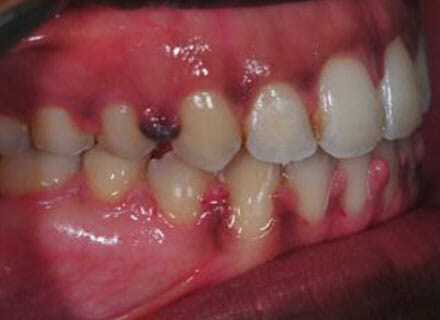

Open bite, protruding upper teeth

How a big open bite can be closed down while at the same time straightening all the teeth and closing gaps! Using clear fixed braces over around 18 months. Please note that the swollen gums in the after photos are what happens if a patient is not cleaning carefully enough or seeing the hygienist during treatment – after careful cleaning and hygiene treatment these gums returned to normal!